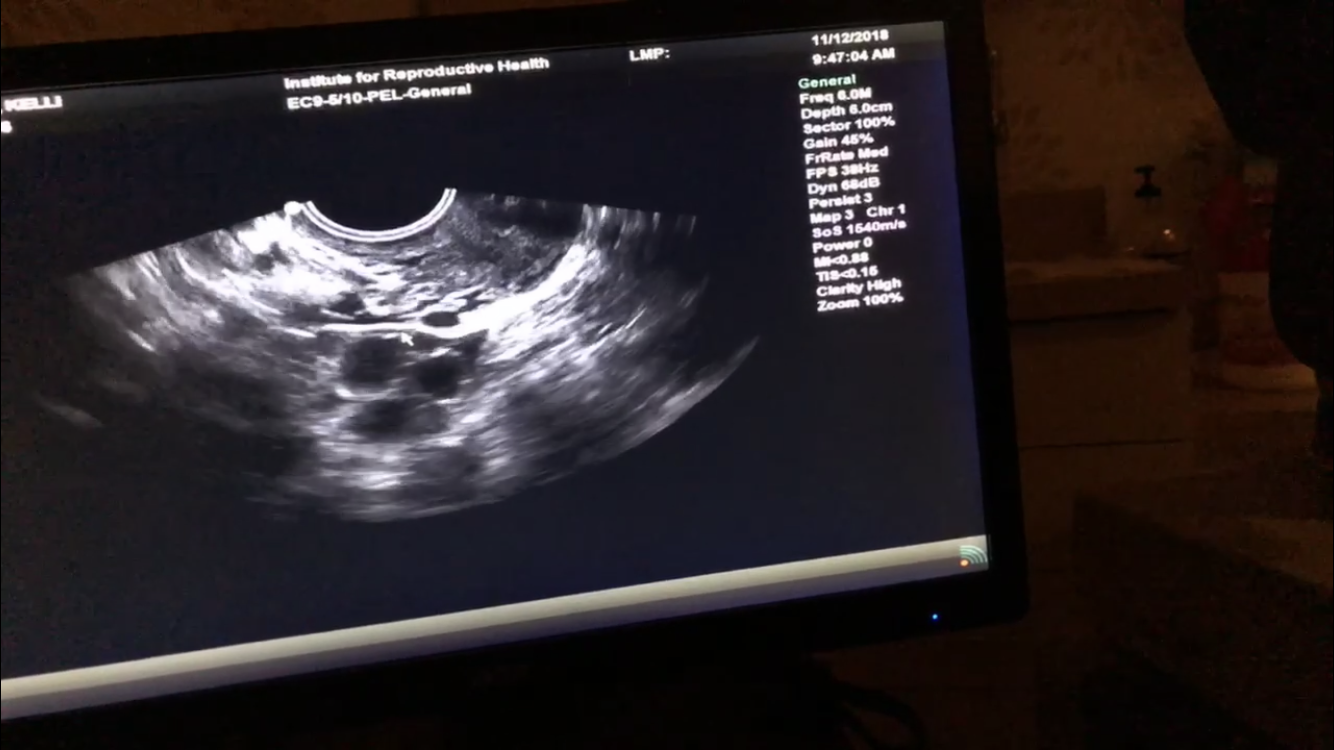

IMG_8783 Previous Next Published November 19, 2018 at 1334 × 750 in WHY I DECIDED TO FREEZE MY EGGS & MY JOURNEY TO FREEZE THEM